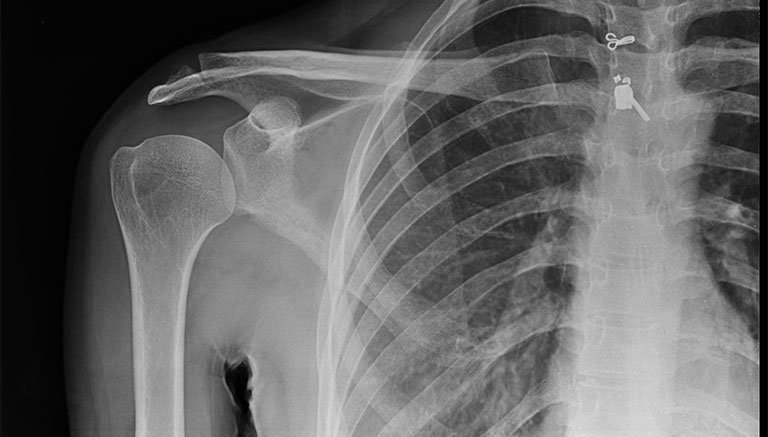

• Các trang thiết bị chẩn đoán hình ảnh như máy X-quang, MRI, CT cần có độ phân giải cao, cho hình ảnh rõ nét, chính xác.

X-quang là một trong những thiết bị phổ biến để kiểm tra tình trạng sức khoẻ của hệ xương khớp